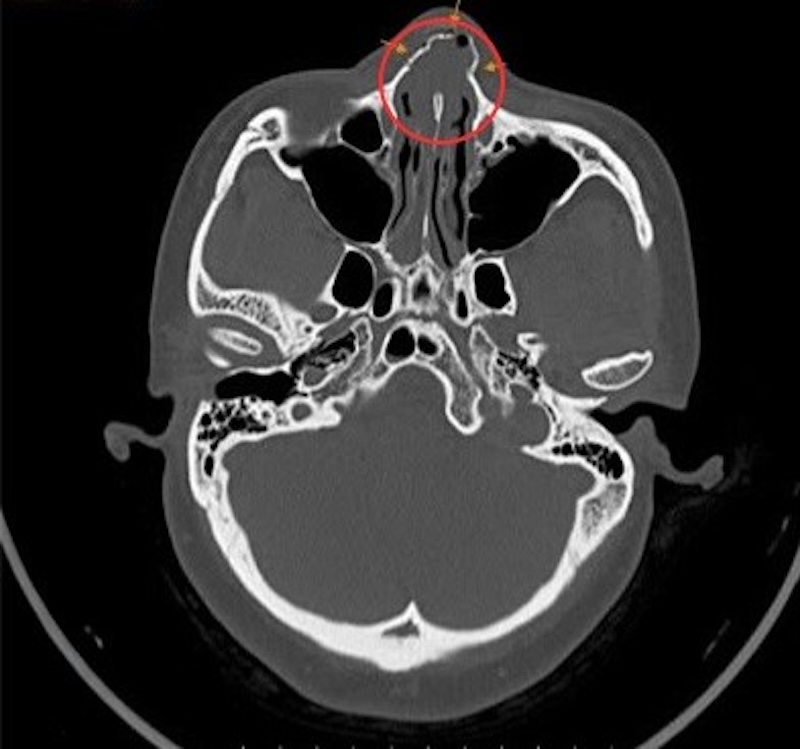

Dr. Chau Tra Linh, from the Ear, Nose, and Throat Center at Tam Anh General Hospital in Ho Chi Minh City, reported that Ms. Han was admitted with controlled nasal bleeding, pain in her nose and left cheek, and tinnitus. An endoscopic examination of her ear, nose, and throat revealed a deviated nasal septum and fluid, including fresh and old blood, in both nasal floor passages. A maxillofacial CT scan confirmed a closed comminuted fracture of the nasal bone, soft tissue injury in the left cheek area, and dental trauma.

CT scan results showed nasal pyramid displacement and comminuted nasal bone fractures. Photo: Tam Anh General Hospital |